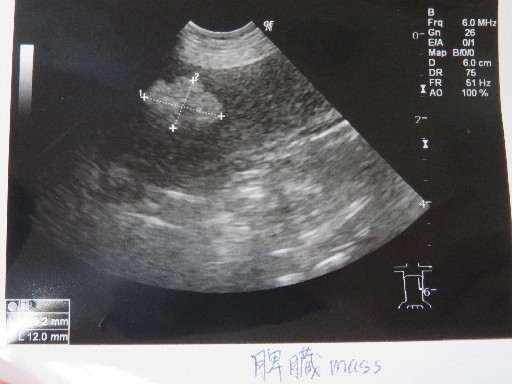

●エコーもしました。

○脾臓のマス、少し大きくなったようですが悪いものにはみえないとのこと。

脾臓の結節が初めて見つかったのは1年4ケ月以上前の2014年6月23日ですし。。。